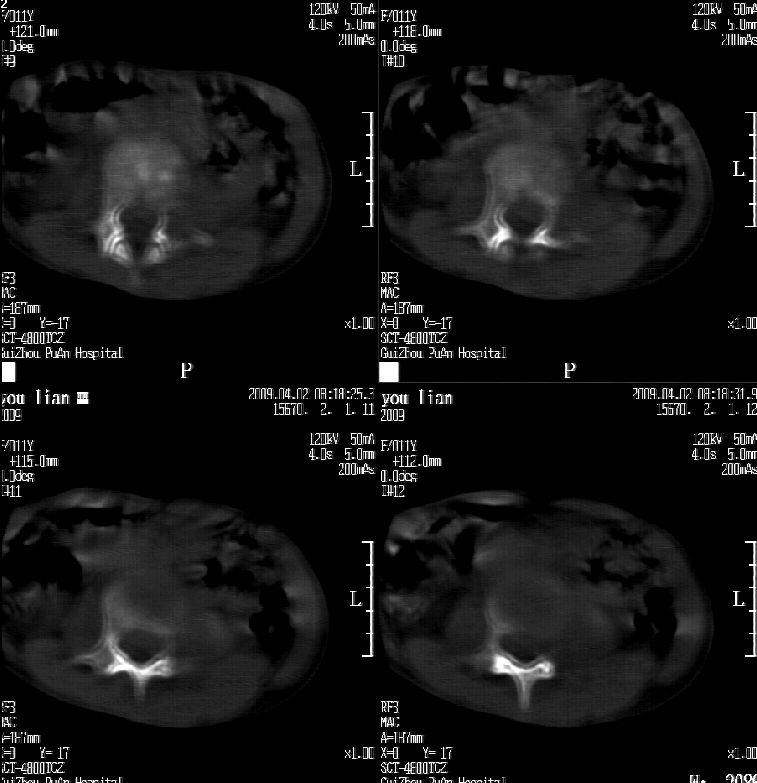

患儿女,11岁,因“腰痛,腰部活动受限10余天”入院。

10余天前,患儿无明诱因出现腰部疼痛,为持续性钝痛,以右侧为著,伴腰部活动受限,有发热,具体体温不详,无寒战、黄疸、盗汗、咳嗽,无尿频、尿急、肉眼血尿。

乍一看像是嗜酸性肉芽肿,但看到ct表现骨质破坏及软组织肿胀考虑结核可能性大,鉴别恶性肿瘤.

本例ct图像太不清楚了,而且不知道有没有传完,如果软组织病变只局限性于那几个层面的话多考虑嗜酸性肉芽肿,其次为其他肿瘤,结核椎旁软组织较广泛,在本例没有太典型表现,建议楼主(孩子父母吧)把所有的软组织窗图像(白色的那种)按顺序全部转上来.

考虑l3嗜酸性肉芽肿。